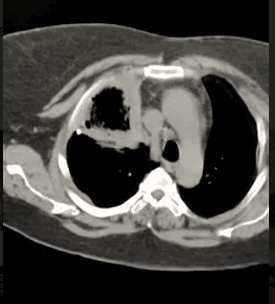

Tac tórax se evidencia neumopatía crónica con lesión ocupante de espacio en lóbulo superior Derecho, de paredes gruesas mayor 1,5 x 1cm aproximadamente hiperdensa, cavitada ( imagen de doble componente) como se muestra en la figura 2.

Figura 2. Tac de tórax corte axial. A) ventana pulmonar se evidencia lesión hiperdensa de paredes gruesas, cavitada B) ventana mediastinica